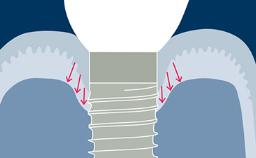

A radiologia é usada em Implantodontia para complementar e confirmar os achados clínicos. As radiografias podem ajudar no diagnóstico, planejamento do tratamento e na revisão de implantes dentários restaurados, em visitas regulares de manutenção. A imagem 3D mostrada aqui demonstra o nível de detalhe que pode ser obtido. No entanto, toda a radiação - incluindo raios-x - acarreta risco de danos aos tecidos e efeitos a longo prazo. Portanto, deve-se considerar os riscos associados à investigação onde a radiografia é planejada, que devem ser equilibrados com os benefícios esperados. Da mesma forma, deve-se considerar uma avaliação das necessidades de diagnóstico e planejamento do caso. A seleção da técnica radiográfica correta deve basear-se no equilíbrio entre as necessidades diagnósticas e o risco.